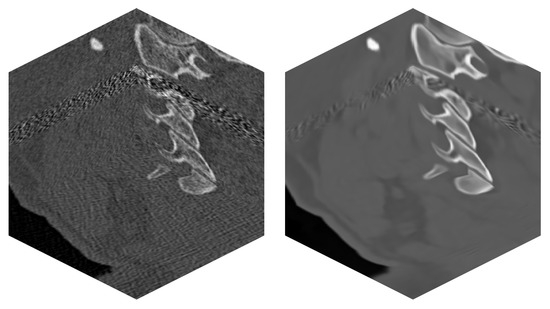

| Method | Quality Measure | ||

|---|---|---|---|

| PSNR | SSIM | RMSE | |

| None | 13.663 | 0.617 | 0.208 |

| RED-CNN | 15.770 | 0.716 | 0.163 |

| OIDN | 22.235 | 0.902 | 0.078 |

| BM4D | 23.547 | 0.921 | 0.067 |